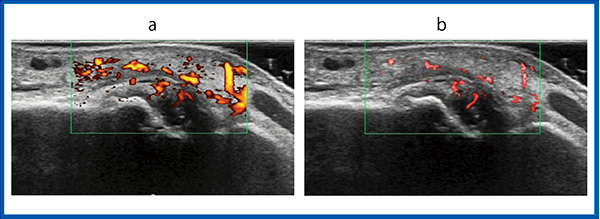

症例3〜5は,SMI画像で血流信号が検出され,パワードプラ画像では血流信号が見られなかったものである。症例3は,左肘頭窩の滑膜炎で,SMI画像では豊富な血流信号が得られているが,パワードプラ画像ではほとんど血流信号が検出できていない(図4)。また,症例4は左手関節橈側の滑膜炎であるが,パワードプラ画像では血流信号を描出できていないが,SMI画像は高い感度で血流をとらえている(図5)。症例5は,左膝外側の滑膜炎であるが,これもパワードプラで検出されない血流信号が,SMI画像では豊富に得られている(図6)。

図6 症例5:左膝外側の滑膜炎

a:パワードプラ画像 b:SMI画像